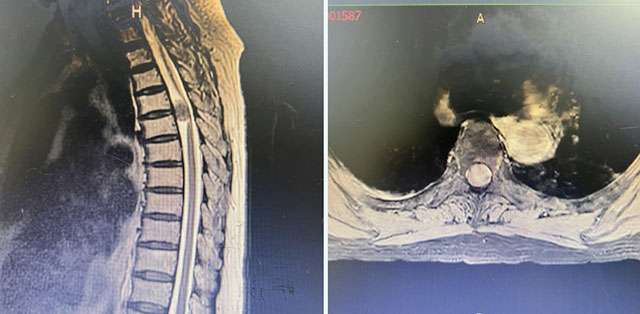

张奶奶近半年来越发觉得双腿麻木、发僵、乏力,走路像踩在棉花上,步态不稳。起初以为是年纪大了,直到出现胸腹部束带般的紧束感,双下肢感觉运动减退,才意识到问题的严重性。就医检查,右下肢肌力2级、左下肢肌力0级,被诊断为胸椎管脊膜瘤。

张奶奶影像检查

脊膜瘤是生长在脊髓表面覆盖的脊膜上的良性肿瘤,好发于胸椎段。它像一个缓慢膨胀的“气球”,逐渐侵占本已有限的椎管空间,压迫脊髓。